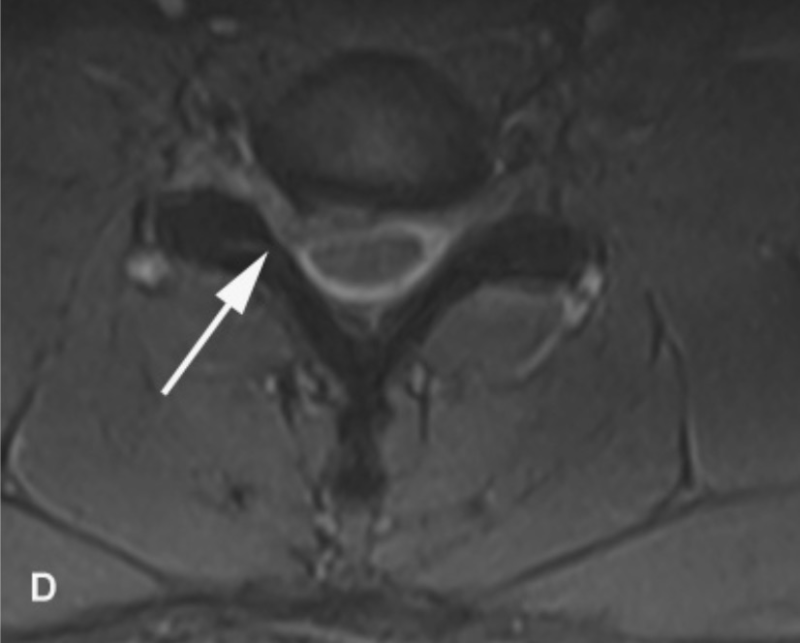

Nhìn chung, các kết quả lâm sàng gợi ý nhiều đến bệnh lý rễ thần kinh C7 bên phải và có thể ảnh hưởng nhẹ ở C6. Các nghiên cứu điện sinh lý đã xác định dẫn truyền vận động và cảm giác thần kinh trụ và thần kinh giữa bình thường ở bên phải và bên trái. Độ trễ sóng F dây thần kinh giữa và trụ bên phải và bên trái nằm trong phạm vi bình thường. Điện cơ kim của cơ tam đầu, nhị đầu, và cơ duỗi các ngón chung bên phải đều bình thường. Đánh giá cơ cạnh cột sống đã bị trì hoãn vì bệnh nhân bị đau. Chụp cộng hưởng từ cột sống cổ [Hình 1] xác định thoát vị đĩa đệm bên phải ở mức C6–7 gây ra hẹp nặng lỗ liên hợp thần kinh bên phải, không có chèn ép tủy sống đáng kể. Bệnh nhân được giới thiệu để cân nhắc phẫu thuật thần kinh lấy bỏ đĩa đệm C6-7.

Hình 1. Hình ảnh MRI cột sống cổ của bệnh nhân được mô tả trong bài này. Hình A là hình T2 đứng dọc cho thấy lồi đĩa đệm C6-C7 lấn vào khoang dưới nhện cổ. Hình ảnh B và C cho thấy đĩa lồi ra trên hình ảnh T1(B) và T2 (C). Có vết ấn nhẹ ở tủy sống nhưng không bị chèn ép đáng kể. Hình D là mặt cắt ngang của đĩa đệm thoát vị cho thấy giảm khoang dưới nhện lỗ liên hợp ở bên phải (mũi tên).